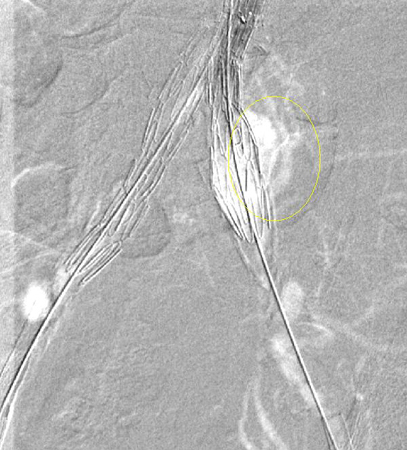

Tipo I:

Fuga en el sitio de inserción (tipo IA en el extremo proximal del endoinjerto u oclusor ilíaco; tipo IB en el extremo distal); por lo general, pueden producirse fugas inmediatas, pero tardías.[Figure caption and citation for the preceding image starts]: Endofuga tipo I en anastomosis distal de la ilíaca izquierda (fuga marcada con un círculo)University of Michigan, específicamente los casos del Dr. Upchurch que reflejan los Departamentos de Cirugía Vascular y Radiología [Citation ends].